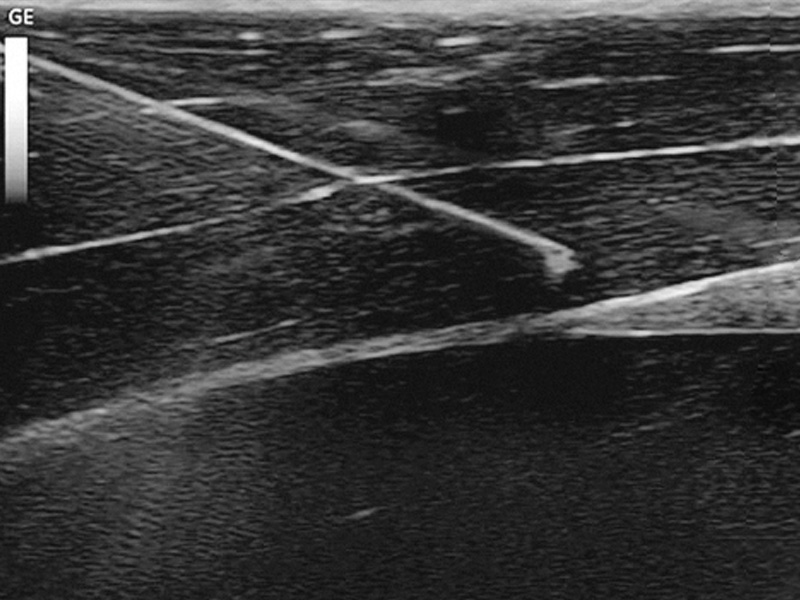

Clinical Thought Leaders: B. Braun Canada has partnered with key opinion leaders in the field of vascular access to provide additional clinical support for the latest practices and procedures in vascular access such as ultrasound guided peripheral IV insertions.

Long Peripheral IV Catheters: Introcan Safety 2 Deep Access is a multi-access blood control long peripheral IV catheter for use with ultrasound guided insertions. This technique can help reduce the need to escalate patients to midlines or PICCs because of failed insertion attempts.